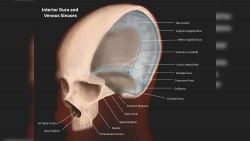

In this class taught by Professor Jim Perkins, students created illustrations of anatomy using a 3D imaging reference, receptor interaction and molecular disease posters. The course explores the use of technologies to provide references for traditional artwork and export models for digital rendering and animation.

Horos Anatomy Image

Students were asked to create an illustration of anatomic structures using Horos imaging software for reference. Horos displays CT and MRI data from actual patients in 3D. Since the Horos models can be rotated in 3D, students created a unique view of anatomic structures — something other than the usual front, back and side views that would be found in a typical anatomy textbook. The final rendering was done in Adobe Photoshop.